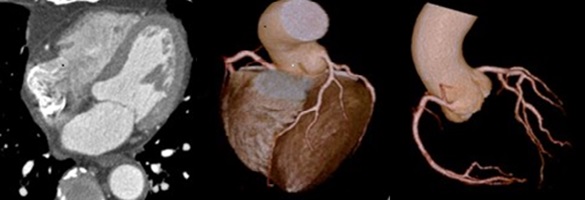

心臓CT検査では従来のCT装置と比べて、被ばく線量が約4分の1に低減され、造影剤量も減量して使用しています。

心臓CT検査